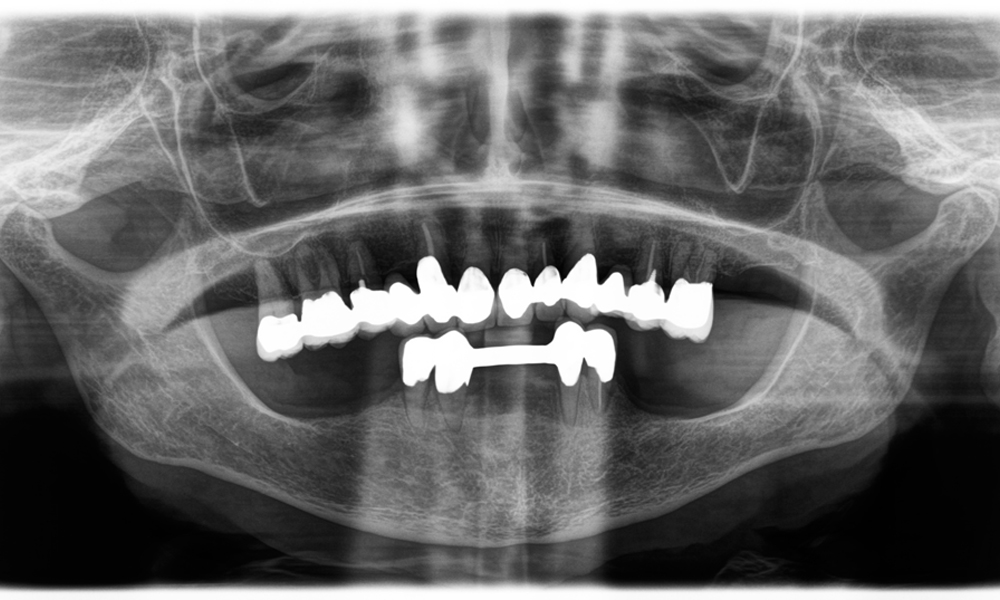

Ein weiteres Beispiel für die klinische Leistungsfähigkeit der Power Edition war der Austausch einer beschädigten Zirkonkrone bei einer 63-jährigen Patientin. Diese stellte sich aufgrund eines abgesplitterten Verblendungsteils ihrer 20 Jahre alten Zirkonkrone an Zahn 6 vor. Trotz der Position im Seitenzahnbereich empfand die Patientin dies als störend und wünschte eine neue Krone.

Die Power Edition ermöglichte eine präzise Schnittführung, wobei das erhöhte Drehmoment und die verbesserte Kühlung dazu beigetragen haben, die Krone ohne größeren Materialverlust zu entfernen. Das Spannsystem und das verbesserte Drehmoment erwiesen sich hierbei als essenziell.